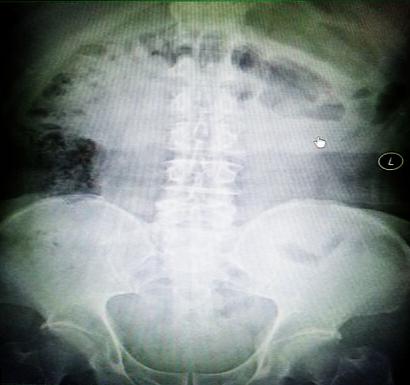

受試患者在結(jié)腸端端吻合術(shù)中,使用我司新研制產(chǎn)品達(dá)到了理想的預(yù)期效果。患者術(shù)后7天、14天X光片顯影,可降解腸道支架均能按研制設(shè)計(jì)的預(yù)期時(shí)間節(jié)點(diǎn)保持應(yīng)有強(qiáng)度,術(shù)后21天X光片顯示可降解腸道支架已完全破碎,并排出體外。在整個(gè)試驗(yàn)過(guò)程中,病患無(wú)任何不良反映,耐受良好。

對(duì)此,一種革命性的腸道端端吻合無(wú)縫對(duì)接手術(shù)方式又向今后大范圍的臨床推廣應(yīng)用邁出了堅(jiān)實(shí)的一步!